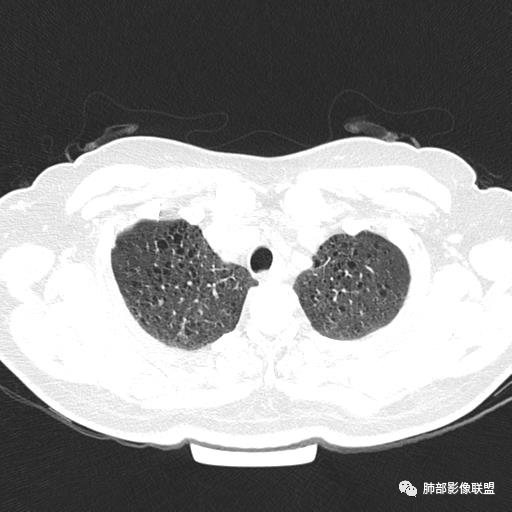

中年女性,不吸烟

双肺弥漫囊腔,累及肋膈角,囊腔形态相对规则单一。

符合LAM

CT平扫示双肺弥漫分布大小不等囊状薄壁透光区,无内、中、外带分布差异,间质稍示增厚。拟LAM

中年女性育龄期妇女,咳嗽气喘,无吸烟史,有苯吸入史。影像:双肺弥漫均匀小囊腔,无明显分布优势,囊腔形态欠规则,壁薄,部分囊腔边缘血管征,伴双肺弥漫磨玻璃影,无结节,考虑lam,鉴别苯中毒肺损伤,囊腔多有分布优势,小叶中心分布为主,形态规整等

女,46,活动性气喘1年。苯吸入史半年。胸部CT:两肺弥漫囊腔,上至肺尖,下至肋膈角,形态类似小囊腔。考虑:LAM,鉴别LIP,BHD,PLCH等。

双肺弥漫大小不一薄壁含气囊腔,囊间肺组织正常,正常肺背景,肺尖肺底受累;青年女性,气喘,支持LAM

双肺多发大小相近的囊状影,分布趋势趋于一致,中年女性,考虑LAM。部分囊内见血管及分隔影,小叶中心性肺气肿代排

CT表现:双肺弥漫大小不等的薄壁囊腔,囊壁<2mm,外形规则,血管影多位于囊腔周围,囊腔之间肺组织正常,随着疾病进展到晚期,囊腔变大、增多,不可胜数,囊腔可融合成较大的囊,与肺气肿相似,形成间质性肺纤维化。部分病例可出现结节影。